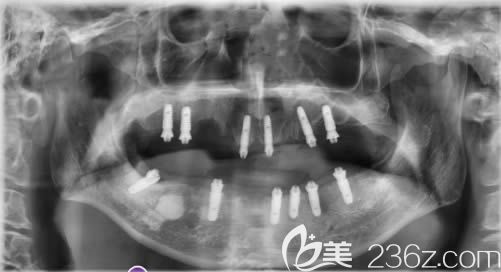

植入口內(nèi)的12顆種植體:↑↑

我是當(dāng)天就戴了牙冠,一共植入了12顆奧齒泰種植體,感覺這次種植牙的費用也不算貴。